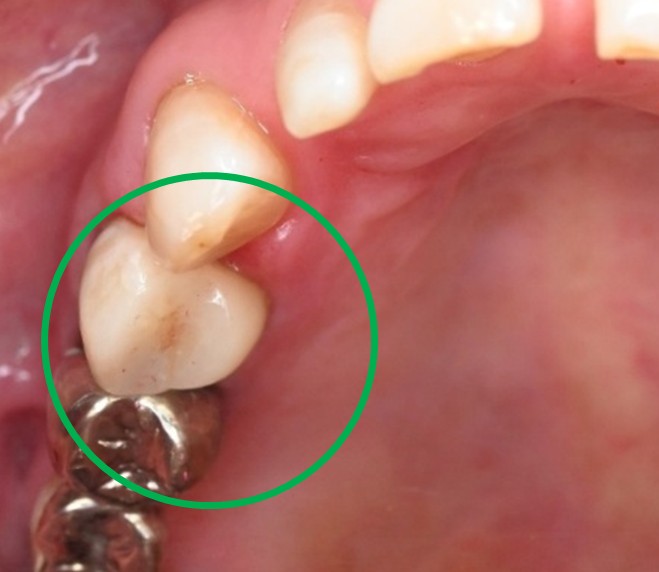

女性 Hさん 60代 (オールセラミック冠・インプラント)

主訴

右下のブリッジがゆらゆら動く。

治療内容

ブリッジの支台になっている奥の歯が、被せ物の中で虫歯になり、支台の役割を果たさず、前方の歯のみで支えられていました。前方の歯をそのままにして、後方の部分を切り離すと、そのまま取れてきました。中は、虫歯で歯根しか残っていない状況でした。この歯は、根管治療後、単独でオールセラミック冠を被せ、歯のないところにインプラントを埋入しました。

所感

今回の治療法には、次の3つの方法があります。

(1)虫歯になっていた歯の根管治療をし、土台を入れ、また再びブリッジにする。しかし、虫歯になっていたほうの歯は、ブリッジの支台として使うには、心もとなく長持ちしない可能性が高く、今度問題が生じたときには抜歯になる。

(2)虫歯になっていた歯に、単独で被せ物をし、歯のないところに1本だけの部分入れ歯を入れる。取り外しの入れ歯なので、自分の歯のような感覚で噛むことはできない。この方法も歯のない部分の負担を欠損の両側の歯に負担してもらうため、長持ちしない可能性が高い。

(3)虫歯になっていた歯に、単独で被せ物をし、歯のないところにインプラントを埋入する。欠損している部分の負担を前後の歯に負担させないので、歯を守ることができる。また、自分の歯と同じ感覚で食事をすることができる。

患者さんは、3つ目の方法を選択されました。一番長持ちし、これ以上歯を失わないためには、最良の方法だと考えます。

オールセラミック冠(失活歯):¥104,500(税込)

インプラント:¥363,000(税込)

合計:¥467,500(税込)

Before

冠の中で大きな虫歯になり支台の役割を果たしていませんでした。

【インプラント埋入前】

冠はブリッジを切断しただけで取れてきました。軟化象牙質を取り除いたところ、歯根しか残っていない状況で保存できるかどうかのぎりぎりのところでした。

After